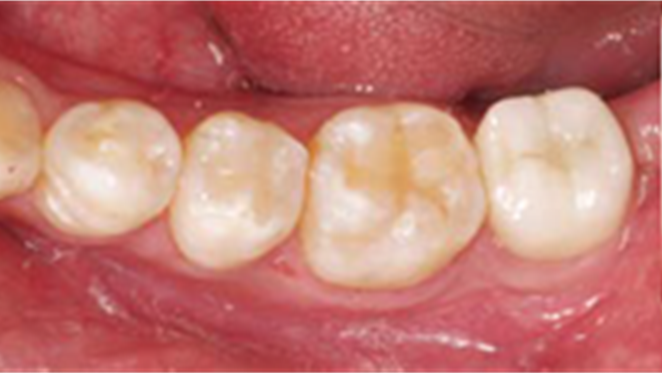

Clinical case: Single molar implant with bone augmentation

- Courtesy of Dr. Jung Sam Lee, Korea -

Keywords

AnyOne, bone augmentation, osteotomy socket, peri-implant tissue, autogenous bone, GBR, single replacement, Auto-Max, Dr. Jung Sam Lee

Products:

AnyOne implant system, Auto-Max